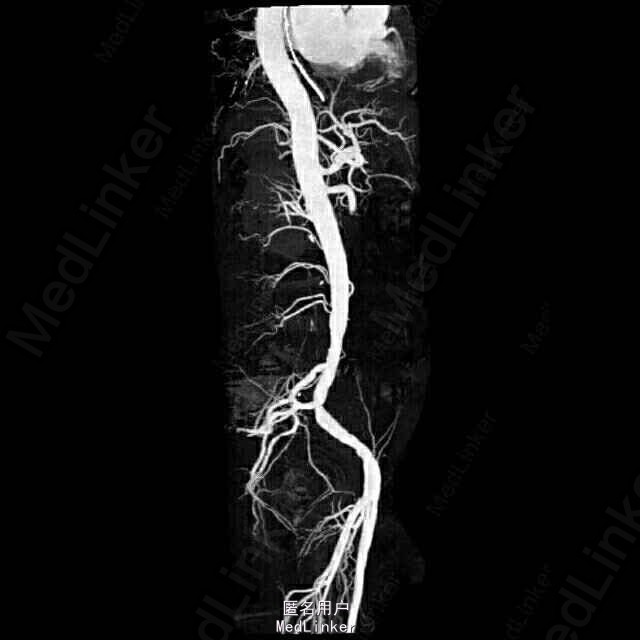

查体:血压:190/110mmHg,巩膜可疑黄染,腹稍膨隆,未见胃肠型及蠕动波,未见腹壁静脉曲张,腹肌软,上腹部压痛明显,无反跳痛,余腹无明显压痛、反跳痛,肝脾肋下未及,墨菲氏征阴性,未及包块,肝肾区无叩痛,移动性浊音阴性,肠鸣音约2-3次/分。 辅助检查:肝功、血脂:AST56U/L,GGT54U/L,LD406U/L,TBA13.9umol/L,AFU61U/L,CHOL6.82mmol/L,HDL1.67mmol/L,LDL4.13mmol/L,APOB1.59g/L。血清胰腺两项:淀粉酶测定165U/L,脂肪酶409U/L。凝血四项:APTT50.1s,TT22.9s。电肾八项:尿素氮9.1mmol/L,肌酐171.5umol/L,葡萄糖14.60mmol/L,CO218.4mmol/L。血常规:白细胞16.00×109/L,中性粒细胞12.72×109/L,红细胞5.52×1012/L,血红蛋白174g/L,HCT0.51,MCH31.6Pg。血沉未见明显异常。胸片+腹平片:心影增大,主动脉硬化。腹部未见气腹及肠梗阻征。彩超提示:1、肝内胆管壁毛糙增厚:考虑肝内胆道感染。2、待排右肾小结石。3、左肾、膀胱、前列腺、脾、胰未见明显异常。4、肠系膜上动脉未见明显异常。全腹平扫+动脉CTA示1、肠系膜上动脉下段及部分分支内可见充盈缺损,分支减少,考虑肠系膜血栓形成可能性大,伴部分小肠缺血改变,请结合临床。2、脾脏小片状低密度影,考虑脾梗塞可能性大,请结合临床。3、考虑不完全性肠梗阻,建议随访。4、目前未见明显腹主夹层动脉瘤,请结合临床。